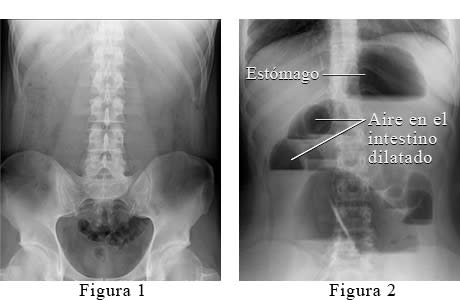

Radiografía abdominal de una obstrucción intestinal